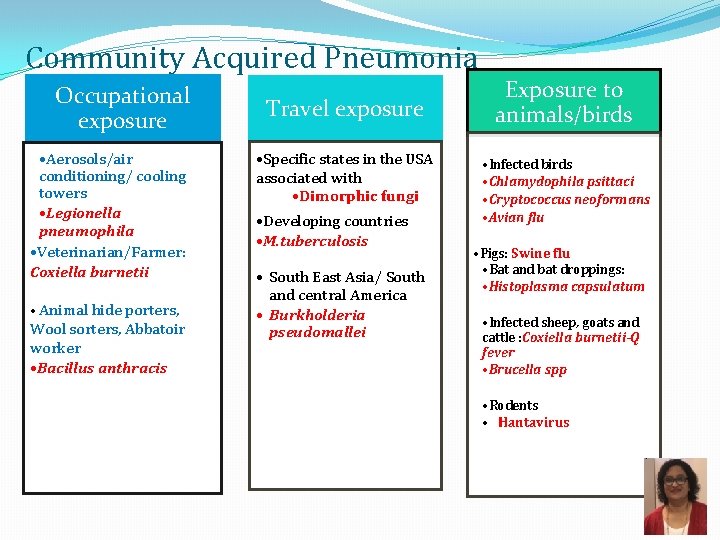

Community Acquired Pneumonia Occupational exposure • Aerosols/air conditioning/ cooling towers • Legionella pneumophila • Veterinarian/Farmer: Coxiella burnetii • Animal hide porters, Wool sorters, Abbatoir worker • Bacillus anthracis Travel exposure • Specific states in the USA associated with • Dimorphic fungi • Developing countries • M. tuberculosis • South East Asia/ South and central America • Burkholderia pseudomallei Exposure to animals/birds • Infected birds • Chlamydophila psittaci • Cryptococcus neoformans • Avian flu • Pigs: Swine flu • Bat and bat droppings: • Histoplasma capsulatum • Infected sheep, goats and cattle : Coxiella burnetii-Q fever • Brucella spp • Rodents • Hantavirus